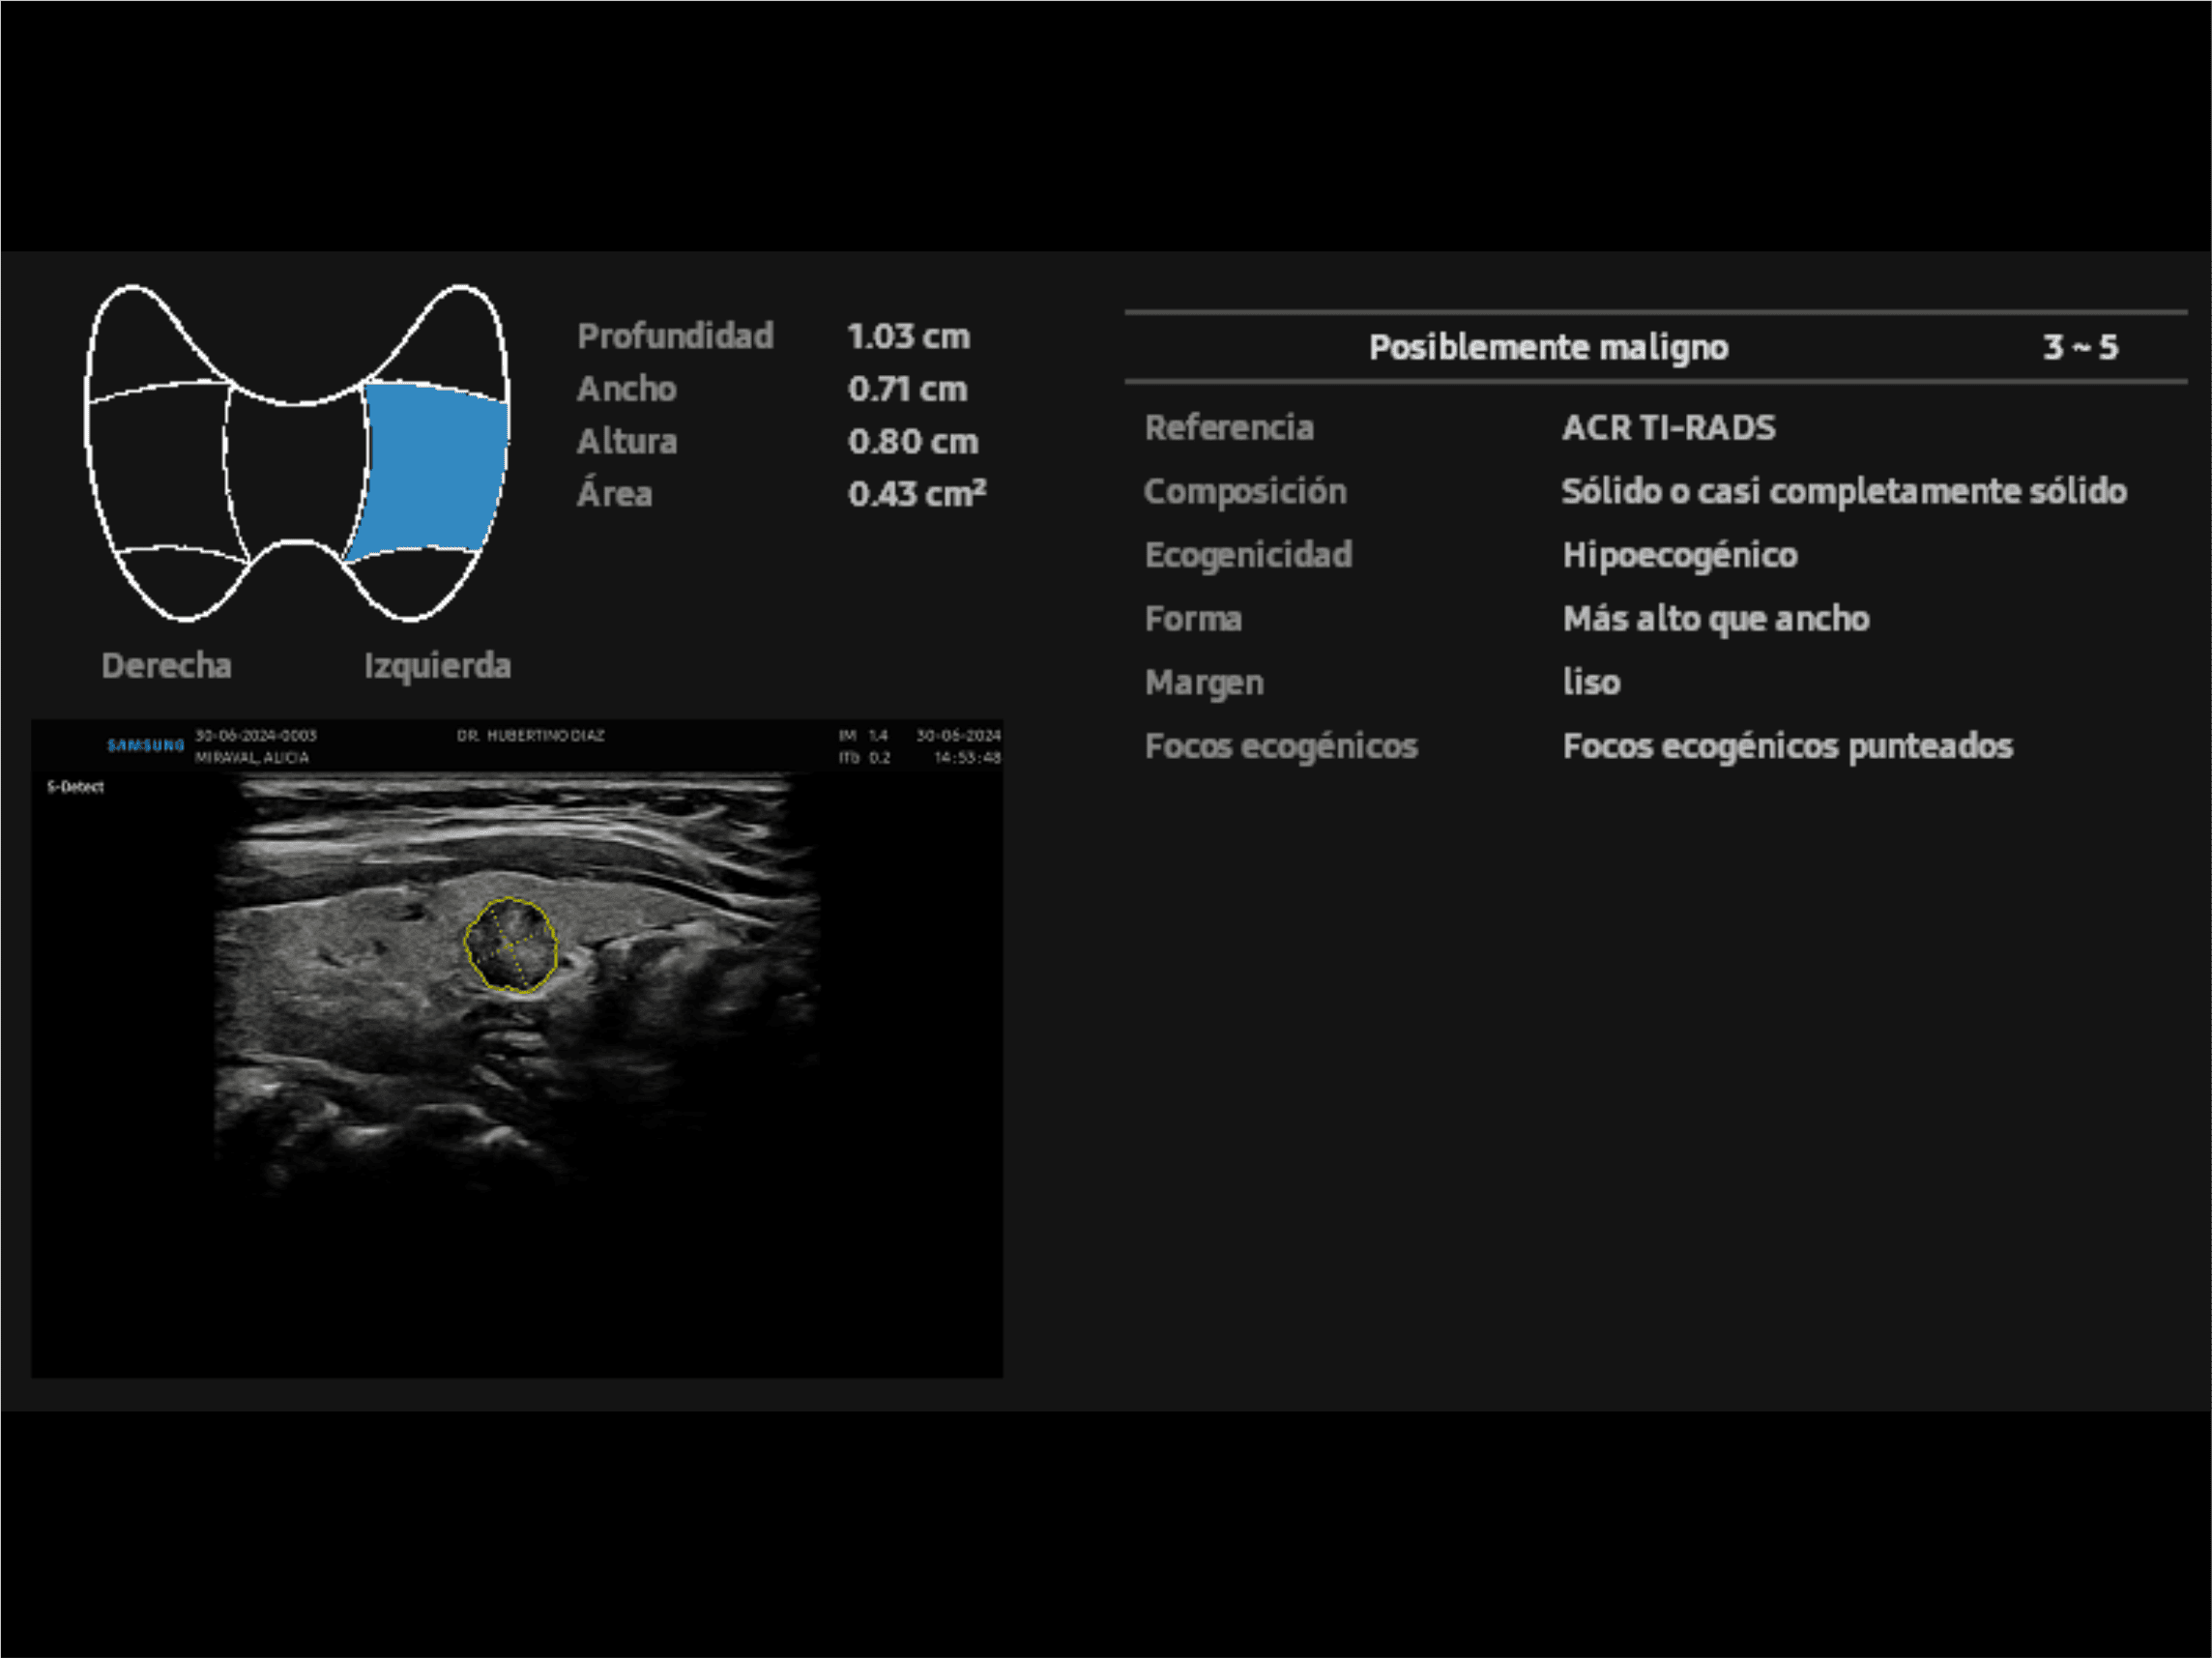

ECOGRAFÍA DE TIROIDES CON INTELIGENCIA ARTIFICIAL

La ecografía de alta resolución constituye el método de elec...